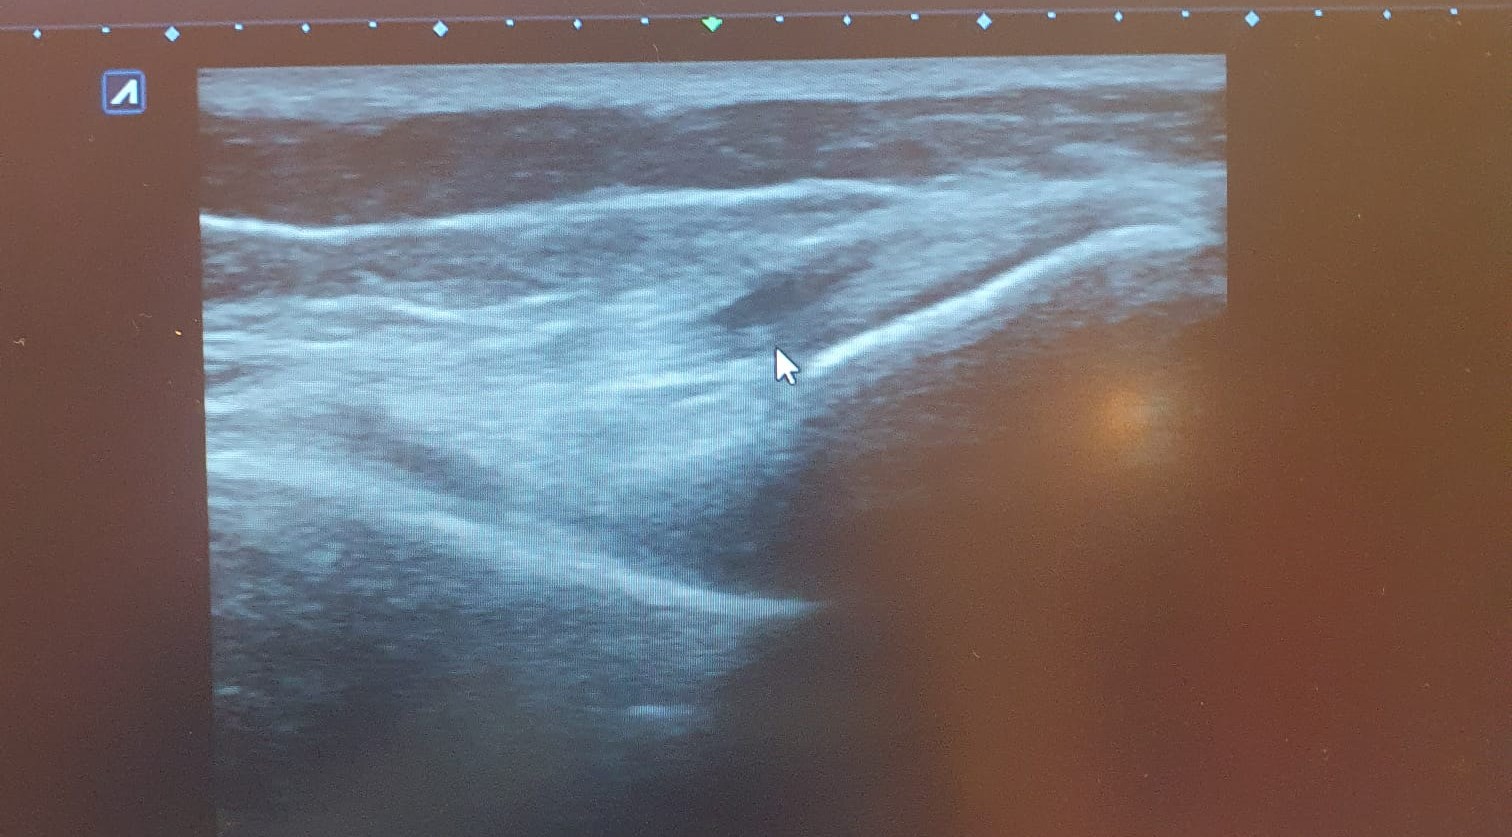

Hallazgos ecográficos

Ecografía de rodilla. Compartimento lateral: imagen anecoica/hipoecoica 10 x 5 mm en zona proximal de ligamento colateral lateral, sugestivo de rotura parcial. Compartimento posterior: imagen anecoica 20 x 30 mm sugestivo de quiste de Baker. No otras alteraciones ecográficas.